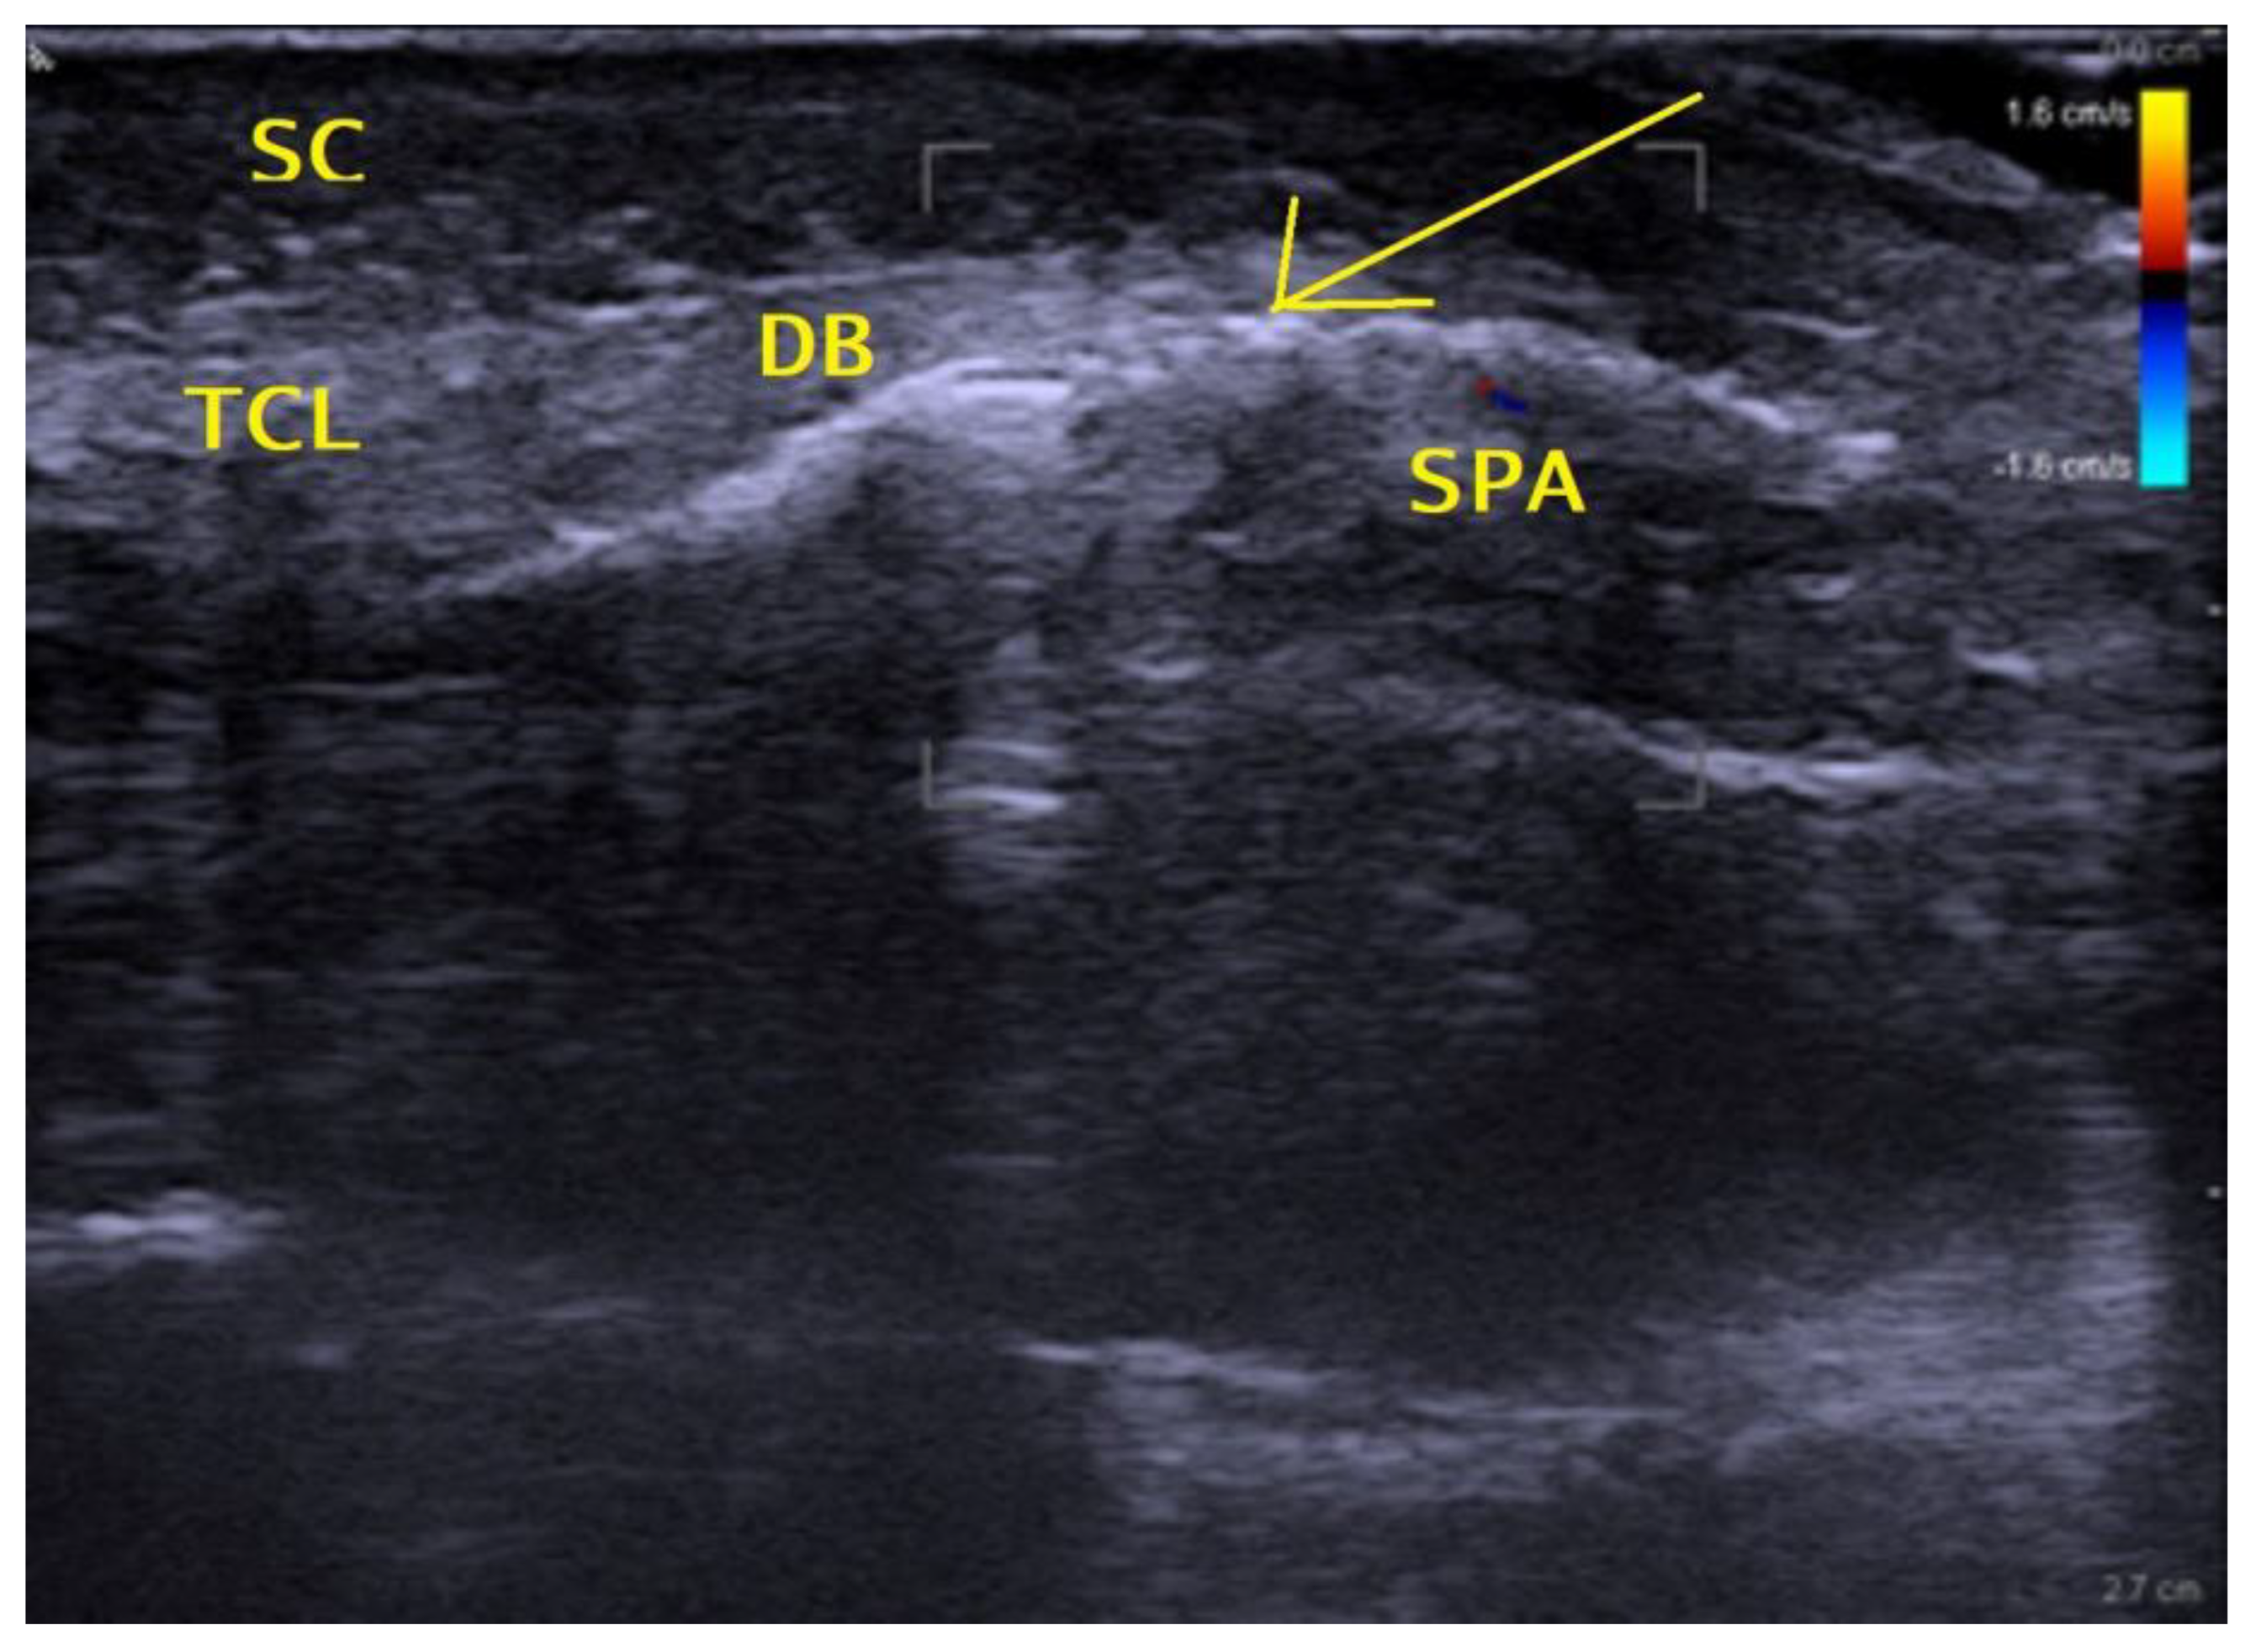

2.2. Surgical Method

2.2.2. Surgical Procedure